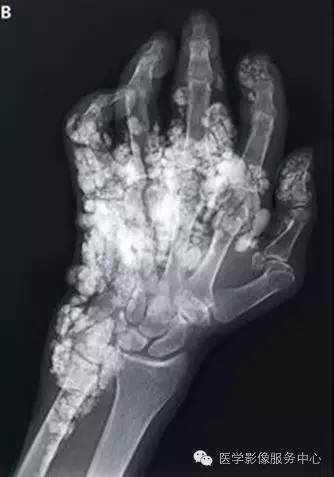

一个74岁的老年男子因全身严重钙化入院就诊。既往有长达16年的系统性硬化病史。

采取的治疗包括高剂量泼尼松、 静脉注射免疫球蛋白和青霉胺。尽管如此患者钙化依然在进展,逐渐导致手指、 手、 脚趾、 右胸和右大腿的功能障碍。外科松解手术虽可暂时缓解疼痛,但是不能控制钙化的进展。查体可见累及手掌以及所有手指未愈合溃疡的广泛软组织钙化,并伴有屈曲畸形。同样的广泛钙化也在X线片和胸部CT检查中被发现。

这种钙化来自于钙羟基磷灰石晶体和其他钙盐的沉积。